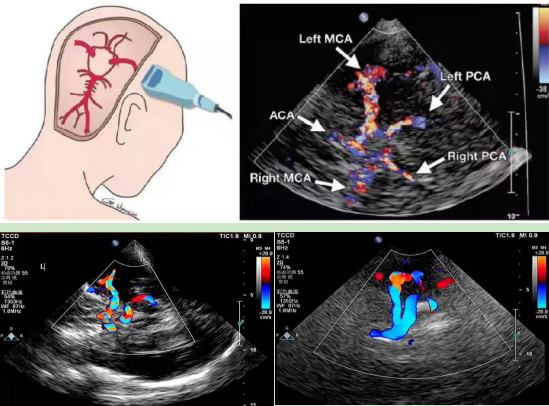

目前用于高危人群筛查的脑颈动脉一体化超声检查,包括经颅彩色多普勒超声(TCCD)和颈部动脉彩色多普勒超声。TCCD是近年来发展的一种无创可视化脑血管超声检查方法。是在TCD成像的基础上,增加二维灰阶成像和彩色多普勒血流成像,能够更直观的识别颅内结构,精准定位颅内血管,通过角度调整,更准确地检测颅内Willis环的血流动力学变化。颈动脉彩色多普勒超声可以测量内-中膜厚度、斑块的大小,评估斑块的稳定性及颈动脉的狭窄程度。